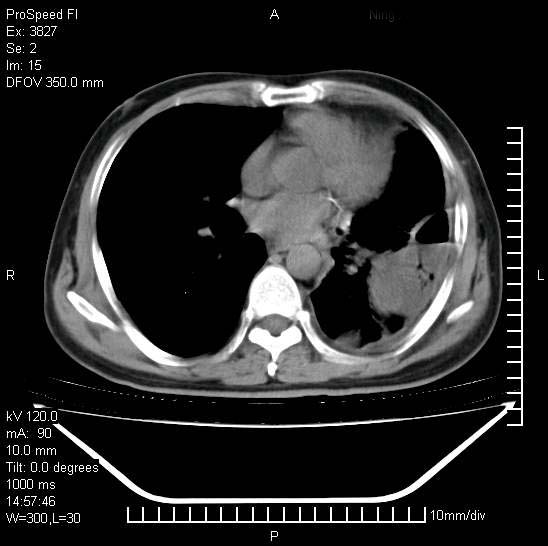

男性,一月前出现右侧肋区疼痛,较剧烈,干咳,无发热,自诉使用抗炎药后缓解,几天前又出现左侧剧烈疼痛,

发热,体温38。9,今天ct,考虑左侧包裹性脓胸,胸腔积液,右上中肺小斑片影,结核/炎症?胸水未见恶性细胞。

左侧肺脓疡,化脓性胸膜炎(脓胸),不支持结核诊断,建议继续抗感染治疗

支持左侧肺脓肿并脓胸,肺内炎症,建议继续抗炎治疗后复查。